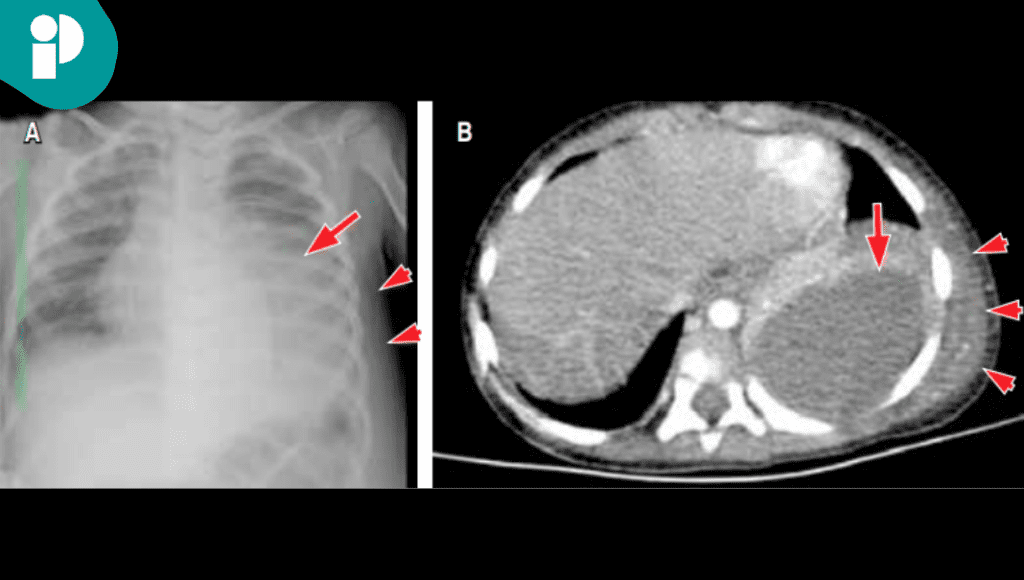

Un reciente reporte clínico describe dos casos en niños que ilustran la diversidad de presentación y la importancia del diagnóstico oportuno. El primer caso correspondió a un niño en edad preescolar, previamente sano, que consultó por fiebre persistente y la aparición de una masa en la región torácica. Los estudios de imagen permitieron confirmar el diagnóstico de empiema necessitatis.

El paciente requirió un manejo quirúrgico con decorticación del lóbulo inferior izquierdo, además de tratamiento antimicrobiano. En este caso, el microorganismo aislado fue Serratia marcescens, una bacteria poco habitual en este tipo de infecciones.

El segundo caso se presentó en un paciente con antecedente de enfermedad granulomatosa crónica, un trastorno inmunológico que aumenta la susceptibilidad a infecciones.

El síntoma principal fue la aparición de masas en la cara anterior y posterior del tórax. Los estudios de imagen revelaron no sólo la extensión del empiema, sino también compromiso óseo. El agente causal identificado fue Aspergillus flavus, un hongo que obligó a un tratamiento prolongado con voriconazol durante seis meses, además de drenaje quirúrgico.